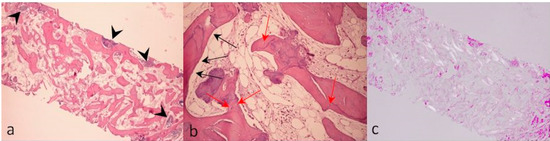

2. Case Description

3. Discussion